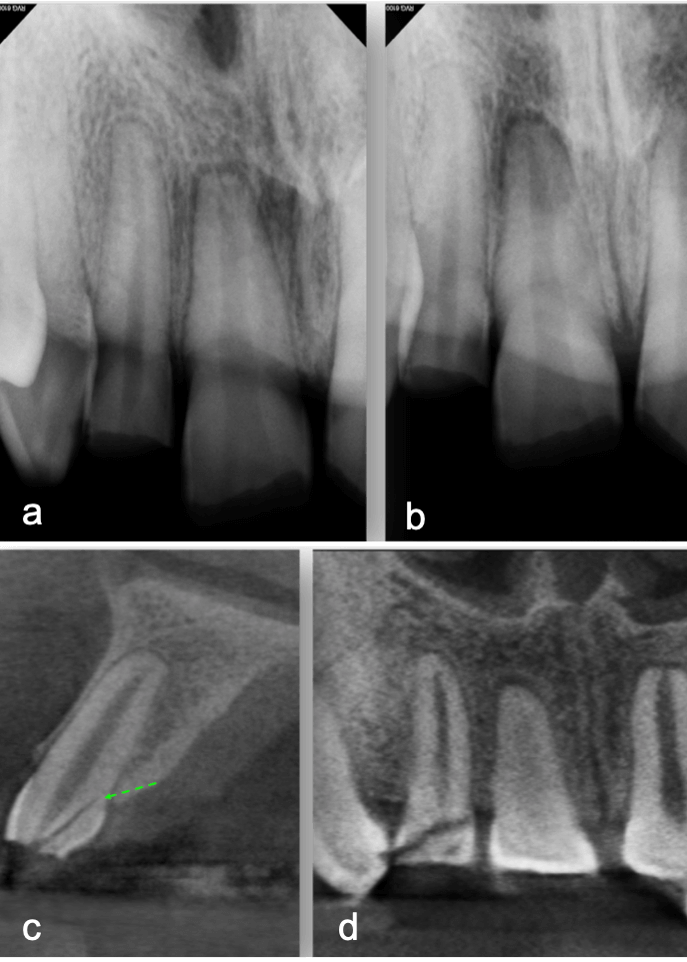

My first “wow” moment with CBCT was during the early years of the technology when scanning a patient after a traumatic dental injury that lead to lateral luxation of the maxillary left central incisor. The CBCT scan was able to produce images that previously had only ever been drawn or imagined. Those stunning 3D images have only gotten better over time. When indicated, 3D imaging provides critical information toward development of the best treatment plan. High-resolution images give endodontists the ability to change course and adapt quickly if needed to achieve better outcomes. Being able to diagnose a predictable failure also avoids unnecessary invasive procedures. For example, cases of root fractures or deep cracks (figure 1). For root canal retreatments understanding the etiology of the disease or failure is critical to obtain a positive outcome. CBCT also aids with enhanced visualization of traumatic injuries, particularly for crown, root fractures and luxation injuries (figure 2). Ultimately, the more accurate and realistic assessments of prognoses, the more predictable and positive outcome for my patients.

a-b. Periapical radiographs from different angles. Patient presented immediate after a traumatic injury to maxillary anterior teeth. Clinical and radi